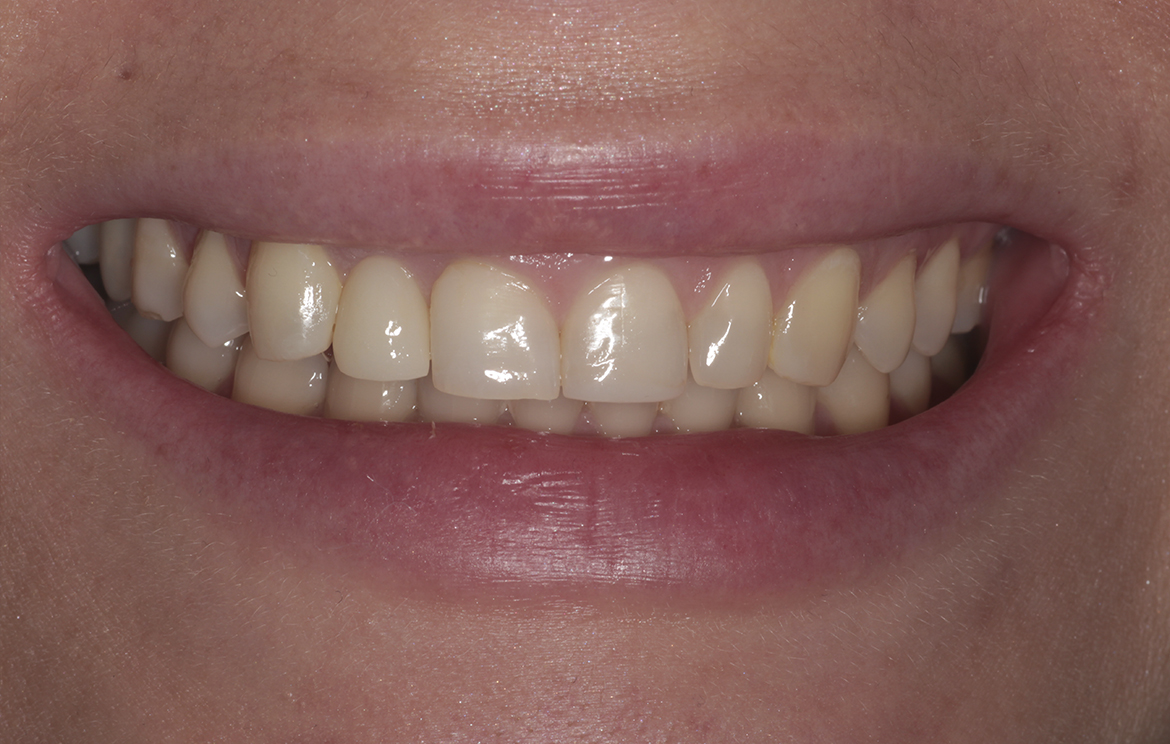

Функциональность и эстетика. Зубы сохраняют свою жевательную функцию и красивый контур улыбки, что особенно важно для передних зубов.

Наши работы